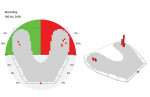

The clinician started by recording a set of diagnostics, which included radiographs, an intraoral scan, photographs, and an OccluSense reading. The initial reading showed that the patient had only a few true points of contact, with much heavier occlusion on the left side of her mouth (Figure 2). Because the patient was in temporary crowns when she presented to the office, a combination of additive dentistry and reduction was used to facilitate a more stable occlusion. An intraoral scan was then taken to record this occlusion, and a new set of temporary crowns were fabricated, with care taken to maintain the occlusion that had just been created.